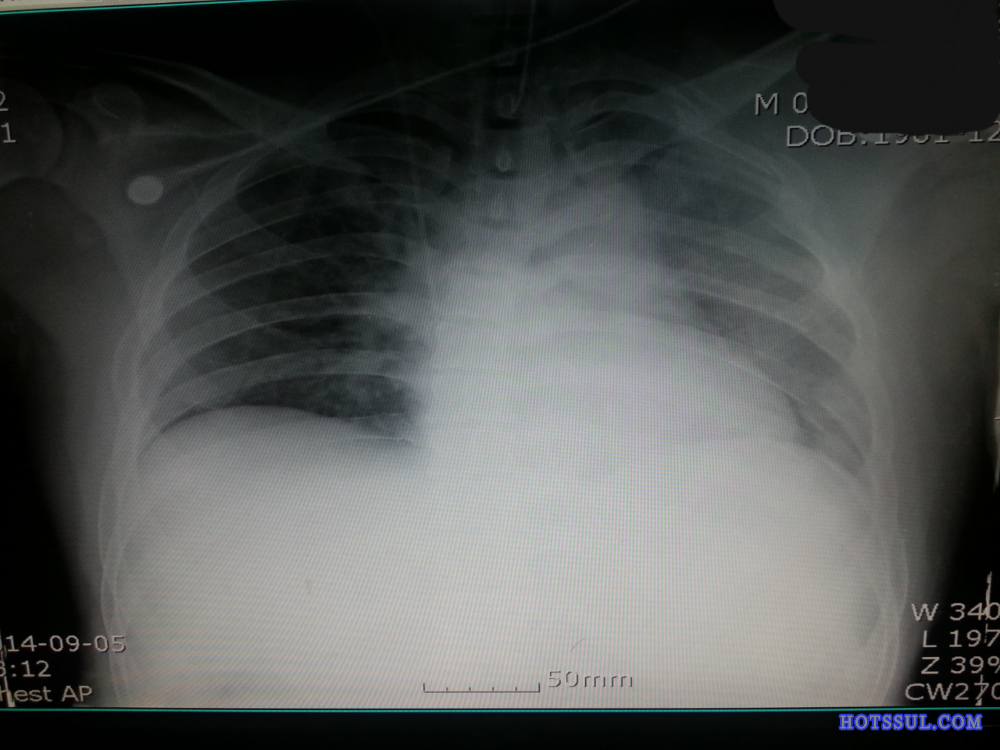

작년 9월에 교통사고가 났다.

위에 있는 짤 두개가 내가 사고 당시에

병원으로 실려와서 찍은 엑스레이 사진이야.

좀 심각했다고 하더라.

당시 부모님한테 연락해주셨던 경찰관님도

중태라고 좀 위험한 상황이라고 부모님한테

말씀하셔서 부모님도 기절할 뻔 했다고 하더라.